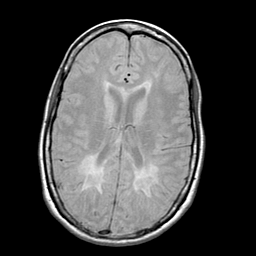

Multiple Sclerosis, MR Study mr-pd -- Slice #13

[Home][Help][Clinical] Slice 13